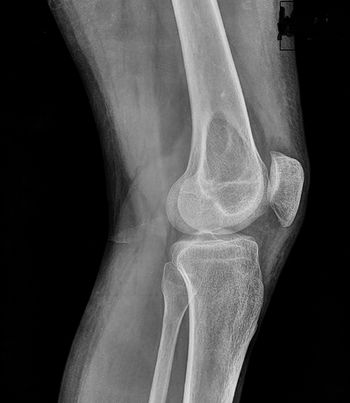

24-year-old male with history of pain in the knee following trauma.